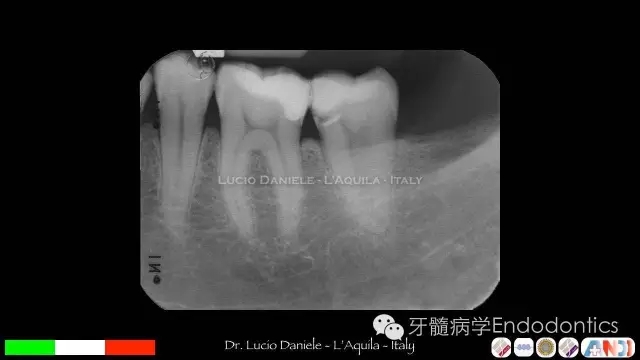

圖10.